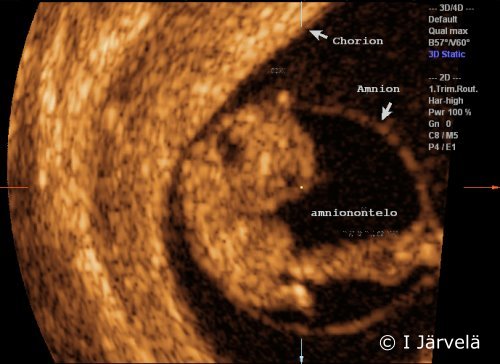

Amnion and chorion (ultrasound scan)

Pregnancy week 8. The amnion and chorion are marked in the ultrasound scan (amnionontelo = amniotic cavity).

Pictures: Ilkka Järvelä; text: Dimitrios Scordas